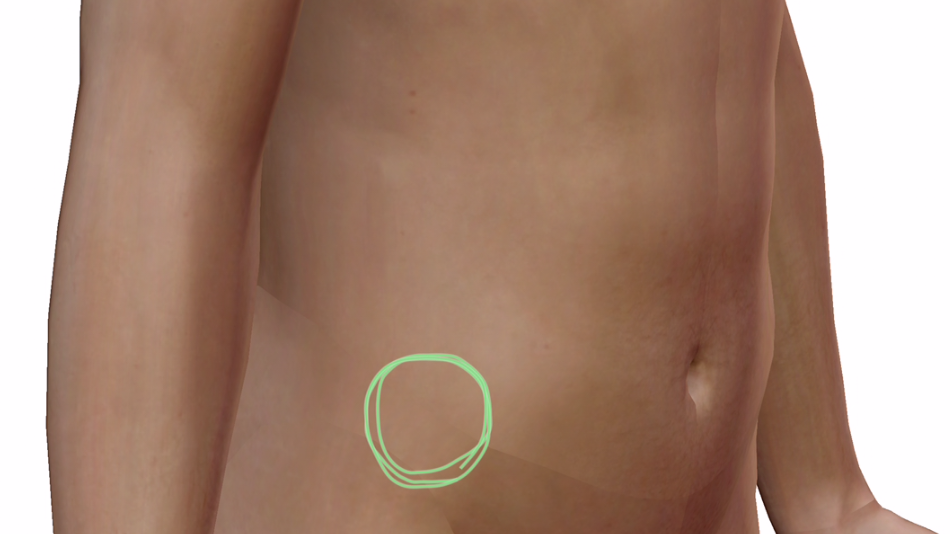

上前腸骨棘ってこちら↓

ここです。

この辺のポコッとしているあたりです。